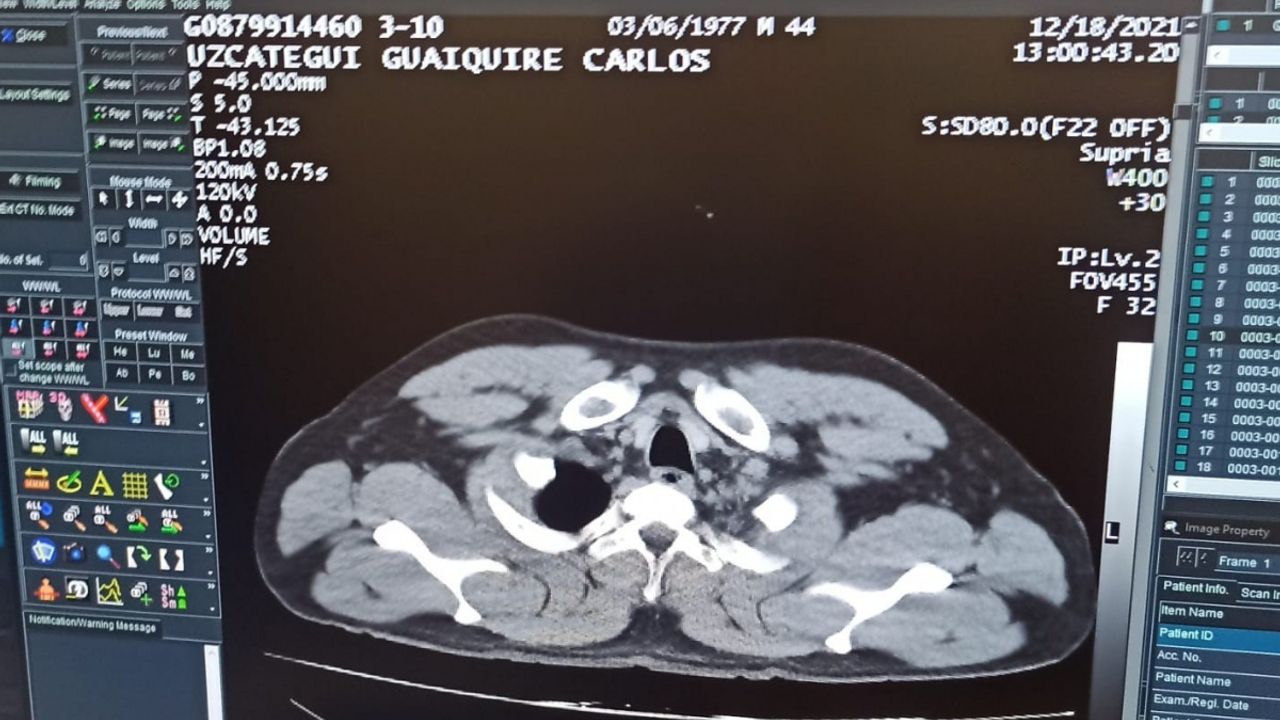

Yapılan ilk muayenenin ardından şahıs tedavisi için hastaneye kaldırıldı. C.M.U.G'un hastanede yapılan tomografi kontrolünde mide ve bağırsaklarında 12 adet kapsül tespit kokain tespit edilmesini üzerine şahıs ameliyata alındı.